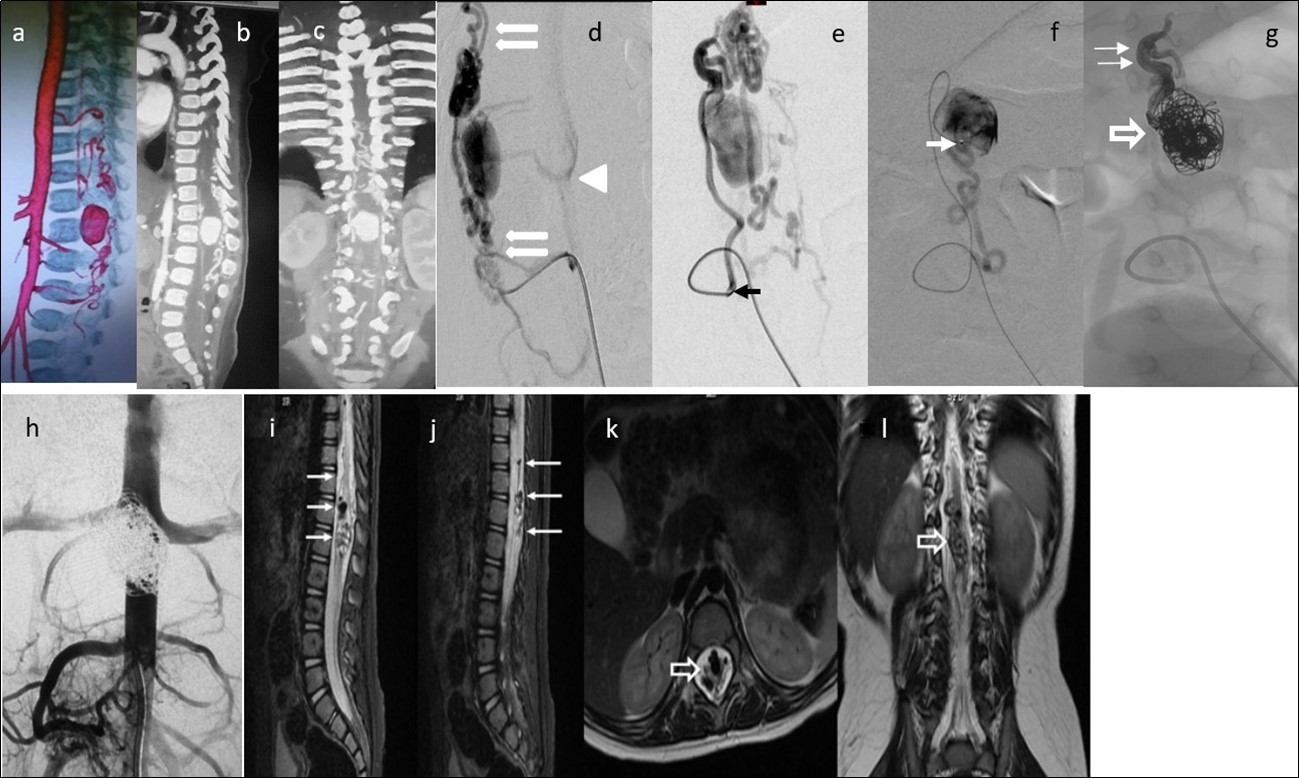

Figure 4.Case 4: a) 3D CTA shows a gigantic venous pseudoaneurysm occupying the spinal canal at the T12-L1 vertebral levels with tortuous veins above and below the lesion. b) and c) 2D reformatted images. d) and e) Selective right L3 angiogram through a 4F guiding catheter (arrow) in lateral and AP projections showing an enlarged PSA feeding a huge venous varix with ascending and descending perimedullary veins (thin arrows) and with segmental epidural draining veins at the fistula level (arrowhead).f) A microcatheter was navigated up to pseudoaneurysm (arrow) g) In the venous sac, 21 GDC coils were deployed (open arrow) and the microcatheter tip was pulled back to the fistulous site followed by Onyx 18 injection to fill up the foot of the ascending draining vein (thin arrows). h) Post-embolization abdominal aortogram (late phase) failed to demonstrate any remaining shunt. i) to l) Multiplanar T2 MR images 6 months’ post-embolization showing absence of flow, and artifacts due to coils and Onyx (arrows). No spinal cord hyperintensity was observed. Patient starting to walk independently with minimal right foot dorsiflexion paresis. He gained complete sphincter control.

Two out of 4 patients were diagnosed and studied preoperatively with both spinal MRI and CT scans, 1 patient with MRI and the other patient with CT/CT Angiography with 3D reconstruction. Large and tortuous flow voids with large to giant venous pouches or pseudoaneurysms (3 of our cases - type c) causing compression of the spinal cord were found lying ventrally and, in another one, posterolaterally to the spinal cord. Hyperintensity in T2W sequences in the spinal cord was noted in all of them. There were no cases where a hemorrhage was exhibited. The angiographic studies confirmed the 4 large or giant pouches at the draining vein fed by ASA and or PSA and ascending (2 cases), descending (1 case) or metameric (1 case) venous drainage. The blood flow was moderate in 1 case and very fast in the other 3 patients (see Table 2 and Figure 1, Figure 2, Figure 3, Figure 4).

We used transarterial approach and a single session achieving complete obliteration of the fistulae while preserving the normal vasculature, mainly the ASA, in all of our 4 cases using either different concentrations of n-bca alone tailored to the blood flow velocity (cases 1,2 and 3), or a combination of coils and onyx 18 (case 4). In this last case, the high flow fistula and the presence of a giant pseudoaneurysm at the venous varix compressing the spinal cord prompted us to deploy coils in the sac and in the draining vein to slow down the blood flow and decrease the chance of distal embolism. To date, we do not have Onyx of higher concentration than Onyx18 available in our country. In high flow macrofistulae, our strategy to slow down the flow to allow casting of the polymerizing embolic mixture in the fistulous site avoiding distal embolism includes lowering mean arterial pressure down to 60-70 mm Hg pharmacologically, by embolizing with concentrations of 66% of n-bca in lipiodol, as well as the placement of detachable coils in the event of very high flow with pseudoaneurysms at or very close to the fistulous site as a first step, to trap the liquid embolic material injected as second step (see Figure 1, Figure 2, Figure 3, Figure 4).